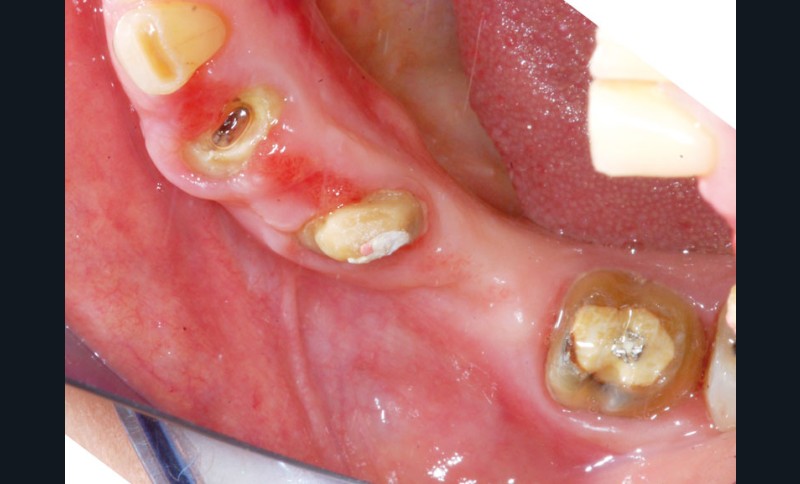

Au maxillaire, 3 implants Astra Tech Implant EV (Dentsply) sont posés en un temps chirurgical. Une empreinte pick-up sera réalisée après 4 mois de cicatrisation.